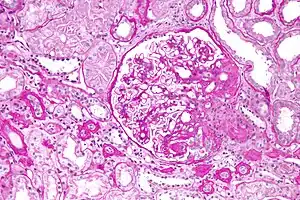

Kidney disease

Hypoalbuminemia can also present as part of the nephrotic syndrome, in which significant quantities of protein are lost in the urine due to kidney damage. Under normal conditions, less than 30 milligrams per day of albumin are lost via the glomerulus.[3] In nephrotic syndrome, protein loss can be as great as 3.5 grams over 24 hours, much of which is albumin, itself leading to hypoalbuminemia.[3] In children, nephrotic syndrome is commonly a primary disease process that is largely idiopathic, although more genetic causes are being identified with the cost and accessibility of whole exome sequencing. After renal biopsy, these syndromes are commonly diagnosed as minimal change disease, membranoproliferative glomerulonephritis, or focal segmental glomerulosclerosis.[9] In adults, on the other hand, nephrotic syndrome is commonly a secondary disease process due to a variety of inciting factors. These inciting factors can be diverse, including toxins, drugs, heavy metals, autoantibodies, post-infectious antibody complexes, or immune complexes formed after malignancies like multiple myeloma.[3]

Albuminuria and resultant hypoalbuminemia can also occur in chronic kidney disease without protein loss levels as high as seen in nephrotic syndrome. Here, albumin loss from the kidneys occur due to decreased glomerular filtration rate (GFR) and subsequent loss of 30 to 300 milligrams of albumin per day. Over the course of months, this can lead to hypoalbuminemia, a common feature of end-stage renal disease.[3] Alterations in fluid distribution and the presence of ongoing inflammation in chronic kidney disease in combination with hypoalbuminemia make fluid status control especially difficult.[5]